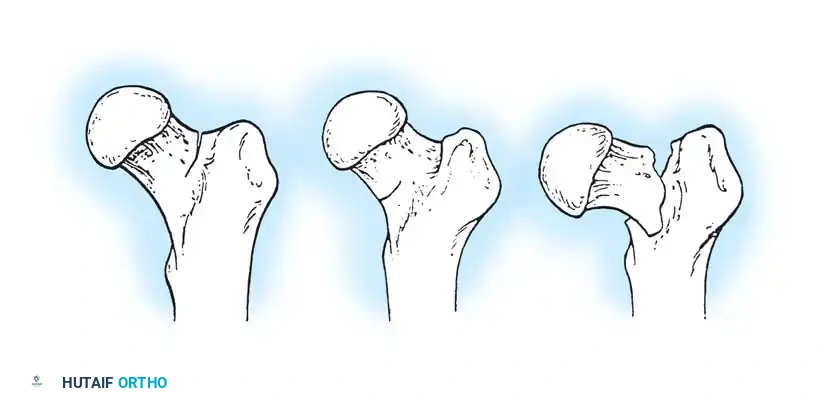

Boyd and Griffin Classification

Boyd and Griffin (1949) classified peritrochanteric fractures into four types based on the ease of reduction and the presence of comminution:

Fig. 52-2: Boyd and Griffin Classification of trochanteric fractures. Types 1 and 2 represent relatively simple patterns, while Types 3 and 4 involve subtrochanteric extension and multi-planar comminution.

- Type 1: Non-comminuted fractures extending along the intertrochanteric line. Simple to reduce and highly stable.

- Type 2: Comminuted fractures along the intertrochanteric line. Reduction is more challenging due to cortical comminution.

- Type 3: Fractures with a subtrochanteric extension. These are inherently unstable and difficult to manage.

- Type 4: Complex fractures involving the trochanteric region and proximal shaft in at least two planes (sagittal and coronal).

Evans Classification

The Evans classification divides fractures into stable and unstable patterns based on the integrity of the posteromedial cortex (the calcar femorale).

* Stable: The posteromedial cortex is intact or can be anatomically reduced.

* Unstable: Characterized by posteromedial comminution, subtrochanteric extension, or a reverse obliquity pattern (where the fracture line extends outward and downward from the lesser trochanter). Reverse obliquity fractures are highly unstable due to the medializing pull of the adductor musculature.

AO/OTA Classification

The AO/OTA system provides a comprehensive alphanumeric categorization:

Fig. 52-4: AO Classification of trochanteric fractures. A1 (simple), A2 (comminuted), and A3 (reverse obliquity/transverse).

- 31-A1: Simple, two-part fractures (Stable).

- 31-A2: Comminuted fractures with posteromedial fragmentation (Unstable).

- 31-A3: Reverse obliquity or transverse fractures extending into the lateral cortex (Highly Unstable).